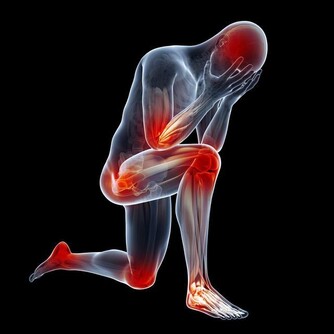

■懶事三:懶得運動,骨質變鬆。

△健康影響:人老了本來就不愛動,加上腿腳不好,很多人會懶得運動,甚至兩三天都不下一次樓。如果長期不運動,人的肌肉會變萎縮,骨關節力量變弱,血液循環減慢,增加骨折、骨關節炎、血栓等風險;不愛動還可能讓老人變胖,而超重和肥胖更會增加「三高」風險,並且,患心腦血管疾病和大腸癌的幾率會增加2~5倍。

△調節方法:經常鍛煉有助預防骨質疏鬆,強健骨骼、肌肉;運動還有益於大腦健康,預防老年癡獃,改善糖尿病、心臟病等多種慢病。

老人鍛煉應動靜結合,鍛煉時感覺不吃力,微微出汗即可;老人還可以多做做家務,哪怕收拾桌子、洗碗這種不費力的小活動,既有益身心,還能美化環境;看書、下棋屬於靜養,可以健腦,但要控製坐著不動的時間,最好半小時就起來走動一下。